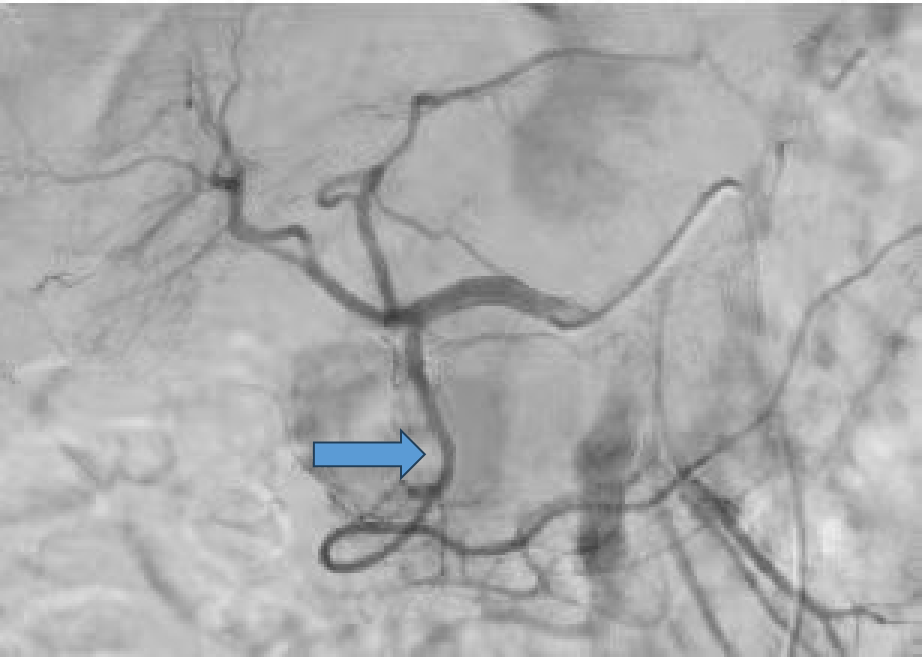

病例:复杂TAAD多次手术后,IIIc型内漏

术后2年随访:动脉瘤增大、左肾支架脱出

★ 大动脉瘤或偏心性动脉瘤术后

如果突然体位变化,有可能主体支架移位导致分支支架从窗口或内脏血管附着处脱出,引起内脏动脉急性阻塞和缺血。

预防措施:

建议至少置入两个分支支架,以固定主体和分支支架。